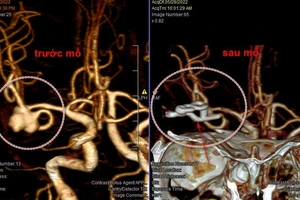

Hi hữu: Vỡ mạch máu não khi đang hát karaoke